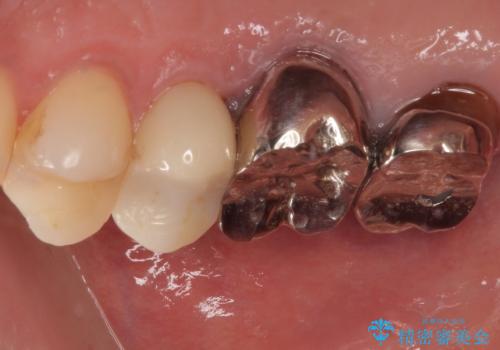

まず残っている詰め物をすべて丁寧に除去し、二次カリエスがないかを確認したうえで、形を整えました。